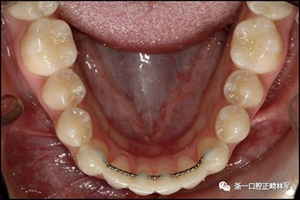

臨床檢查顯示固定保持器完好,弓絲沒有斷裂(圖13)。在下頜右側(cè)中切牙唇側(cè)和鄰近側(cè)切牙的舌側(cè)注意到有牙齦退縮。這些牙齒在退縮方向上存在顯著的扭矩差異。下頜的左側(cè)尖牙頰側(cè)錯(cuò)位,而右側(cè)尖牙舌側(cè)傾斜。三維射線照片證實(shí)了下頜右側(cè)尖牙面?zhèn)妊啦酃菃适?,右?cè)中切牙的喪失程度較輕。右側(cè)側(cè)切牙根也從舌側(cè)骨面上扭轉(zhuǎn)出來(圖14)。

圖13.粘合到尖牙和切牙上的柔性螺旋弓絲保持器,伴有牙齦退縮和附著喪失,中切牙之間嚴(yán)重的扭矩差異以及兩顆尖牙的橫向移動和扭矩。牙周問題和牙齒移動的嚴(yán)重程度均為牙周正畸聯(lián)合治療的指征:A,正面視圖; B,咬合面視圖。